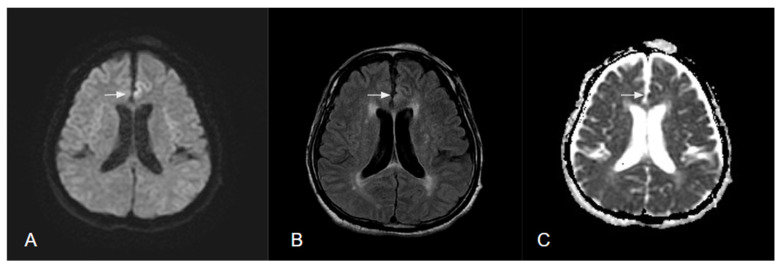

癫痫是一种常见的神经系统疾病;全世界有1%的人患有癫痫。在临床环境中区分癫痫发作与其他急性神经系统疾病可能具有挑战性。大约三分之一的患者患有目前抗癫痫药物治疗不能很好控制的耐药癫痫。手术治疗是潜在的治愈,如果癫痫灶准确定位。扩散加权成像(DWI)是一种先进的磁共振成像技术,它对水分子的扩散很敏感,并提供有关组织微观结构的额外信息。定性和定量分析周周、后周和间期弥散图像有助于癫痫发作的鉴别诊断和癫痫病灶定位。本文综述了DWI的基本原理及其相关技术,如表观扩散系数、弥散张量成像和神经束造影,以及它们在鉴别诊断、癫痫病灶确定和预后预测方面对癫痫的影响。

Epilepsy is a common neurological disorder; 1% of people worldwide have epilepsy. Differentiating epileptic seizures from other acute neurological disorders in a clinical setting can be challenging. Approximately one-third of patients have drug-resistant epilepsy that is not well controlled by current antiepileptic drug therapy. Surgical treatment is potentially curative if the epileptogenic focus is accurately localized. Diffusion-weighted imaging (DWI) is an advanced magnetic resonance imaging technique that is sensitive to the diffusion of water molecules and provides additional information on the microstructure of tissue. Qualitative and quantitative analysis of peri-ictal, postictal, and interictal diffusion images can aid the differential diagnosis of seizures and seizure foci localization. This review focused on the fundamentals of DWI and its associated techniques, such as apparent diffusion coefficient, diffusion tensor imaging, and tractography, as well as their impact on epilepsy in terms of differential diagnosis, epileptic foci determination, and prognosis prediction.